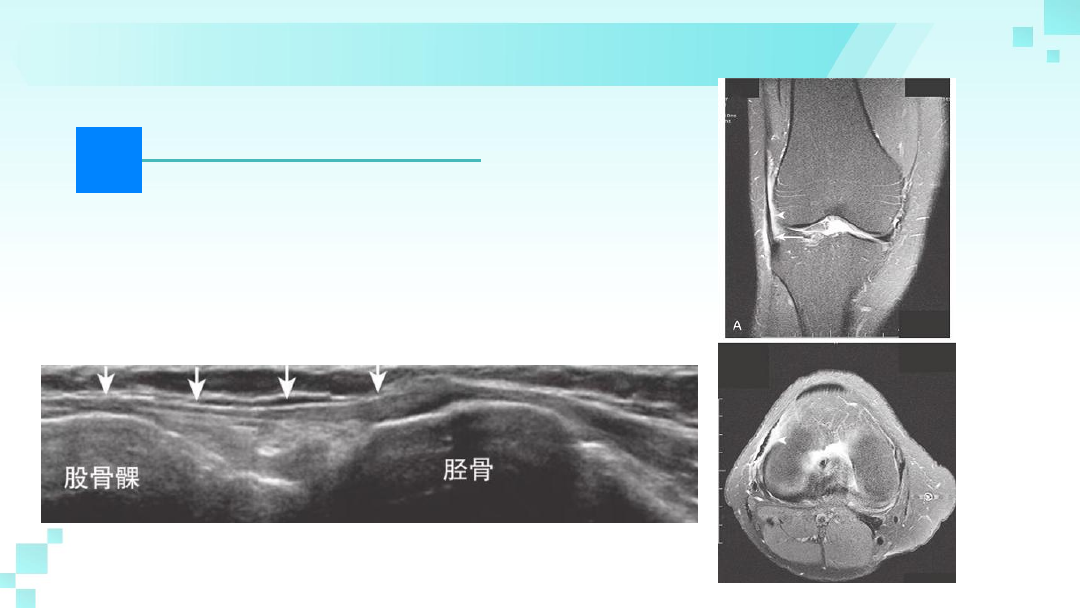

跑步膝的检查

神X线、磁共振、彩超

膝部X线检查可能会发现滑囊和相关结构

(包括髂胫束韧带)的钙化,提示有慢性

炎症。如果考虑是跑步者膝、髂胫束滑囊

炎、膝关节内部紊乱、隐匿性肿瘤等需要

进行MRI检查。超声成像可能有助于明确

诊断。